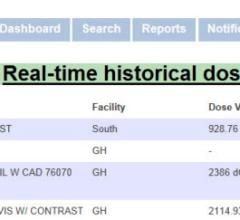

PHS Technologies Group LLC, a division of PACSHealth LLC, announced that Radiology Partners, the largest hospital-based radiology group in the United States, will begin offering PHS’s DoseMonitor to monitor patient radiation exposure.